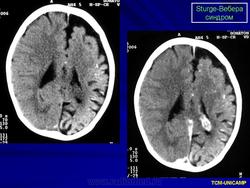

Компьютерная томография пациента с болезнью Штурге - Вебера